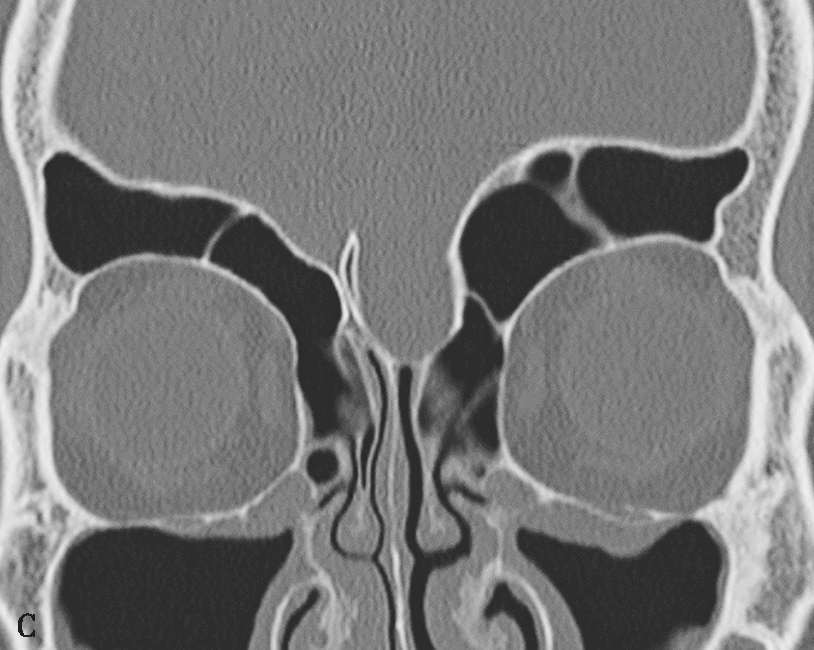

1.上颌窦发育不全

根据CT表现可将其分为三型:一型,只有轻度发育不全,钩突和筛漏斗正常;二型,上颌窦体积轻至中度减小,并有钩突发育不全或筛漏斗缺如;三型,上颌窦缺如,仅由1个嵴组成,并有钩突缺如。上颌窦发育不全的同侧鼻腔和眼眶常扩大。上颌窦不对称在平片上就可显示,但是窦腔较小可被误认为有慢性上颌窦炎的窦腔,尤其当患者有持续性上呼吸道症状时更易误诊。

2.有分隔的上颌窦

可由纤维或骨性分隔分成2个不对称的部分,这些隔常从眶下管到窦的外侧壁,把上颌窦分成外上和内下部分。此变异应该引起注意,因为分隔可使上颌窦手术引流不完全而使病变残留。双上颌窦是少见的变异,在一侧上颌骨有2个独立的窦腔并通过独立的开口引流到中鼻道(图1-3-8)。

图1-3-8 上颌窦解剖变异

A.右上颌窦未发育;B.上颌窦发育小;C.磨牙突入上颌窦;D.双侧上颌窦副口